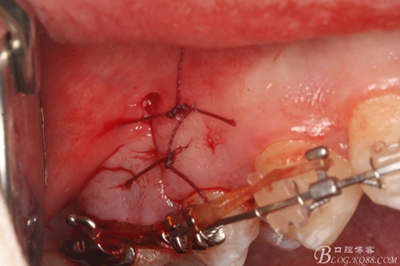

圖23.僅做頰側垂直切口縫合

圖24.合面觀:微創(chuàng)小切口,15牙根完整取出,創(chuàng)傷小。